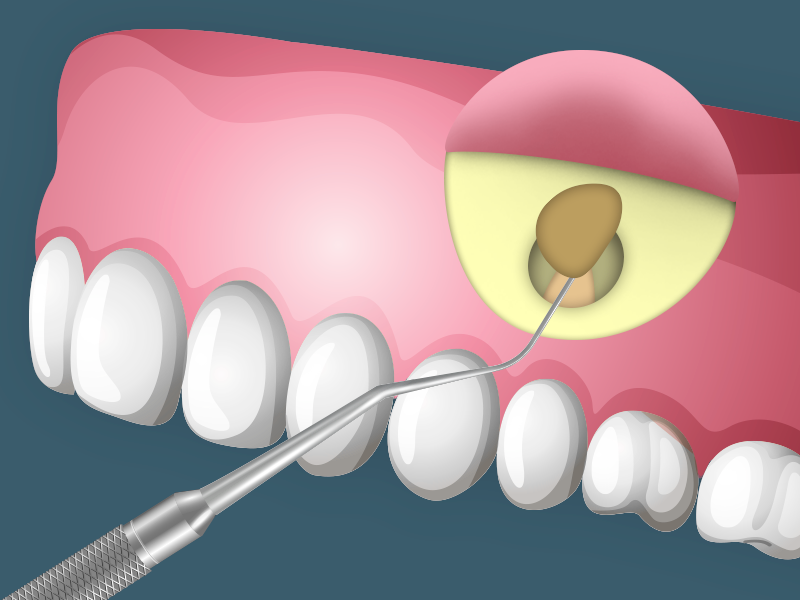

Apicectomia

O que é apicectomia? É uma cirurgia que tem por finalidade a remoção da lesão que se forma no ápice (ponta da raiz do dente). Existem dois tipos básicos de cirurgia: uma que apenas remove a lesão através de curetagem e outra que, além disso, remove o ápice da raiz. Por que ocorre essa lesão […]